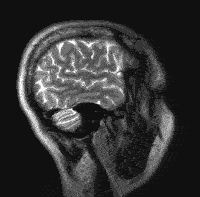

Een MRI onderzoek maakt gebruik van röntgenstralen maar van een sterk magnetische veld en radiofrequentie golven. Net als bij de CT-scan moet de patiënt zo stil mogelijk liggen in een tunnel. De MRI is de tunnel is nauwer en langer dan bij de CT-scan. Sommige patiënten ervaren dit als wat benauwend. Als de patiënt in de MRI ligt kan de achter een glazen raam in een andere kamer zittende radiologie medewerker via een microfoon en speakers praten met de de patiënt. De patiënt krijgt ook nog een schakelaar in de hand krijgt waarmee een bel kan doen afgaan wanneer hij contact wil maken met deze onderzoekers. De patiënt krijgt oordopjes in de oren voor het lawaaierige monotone geluid dat deze machine maakt en in de meeste MRI's kan de patiënt tegenwoordig ook naar de radio luisteren ter afleiding. Een MRI-scan van de hersenen duurt beduidend langer (15-30 min) dan een CT-scan (5-10 min), maar biedt meer gedetailleerde informatie van de hersenen dan een CT-scan.

Een MRI-scan maakt op verschillende manieren foto's van dunne laagjes van de hersenenen, zoals van boven naar beneden en van de ene zijkant naar de andere zijkant. Deze foto's worden opgebouwd uit de verkregen signalen die door de computer van de MRI-scanner worden omgezet. Deze computer kan daarbij de samenstelling van de verschillende weefsels berekenen en ze uittekenen in de vorm van een doorsnede. Ook bij de MRI wordt vaak gebruik gemaakt van contrastmiddel. Na toediening van contrastvloeistof (toegediend via een infuus in een bloedvat in de elleboogsplooi) kunnen sommige hersentumoren aankleuring laten zien. Dit zegt iets over de aard en vooral over de doorbloeding van de hersentumor.